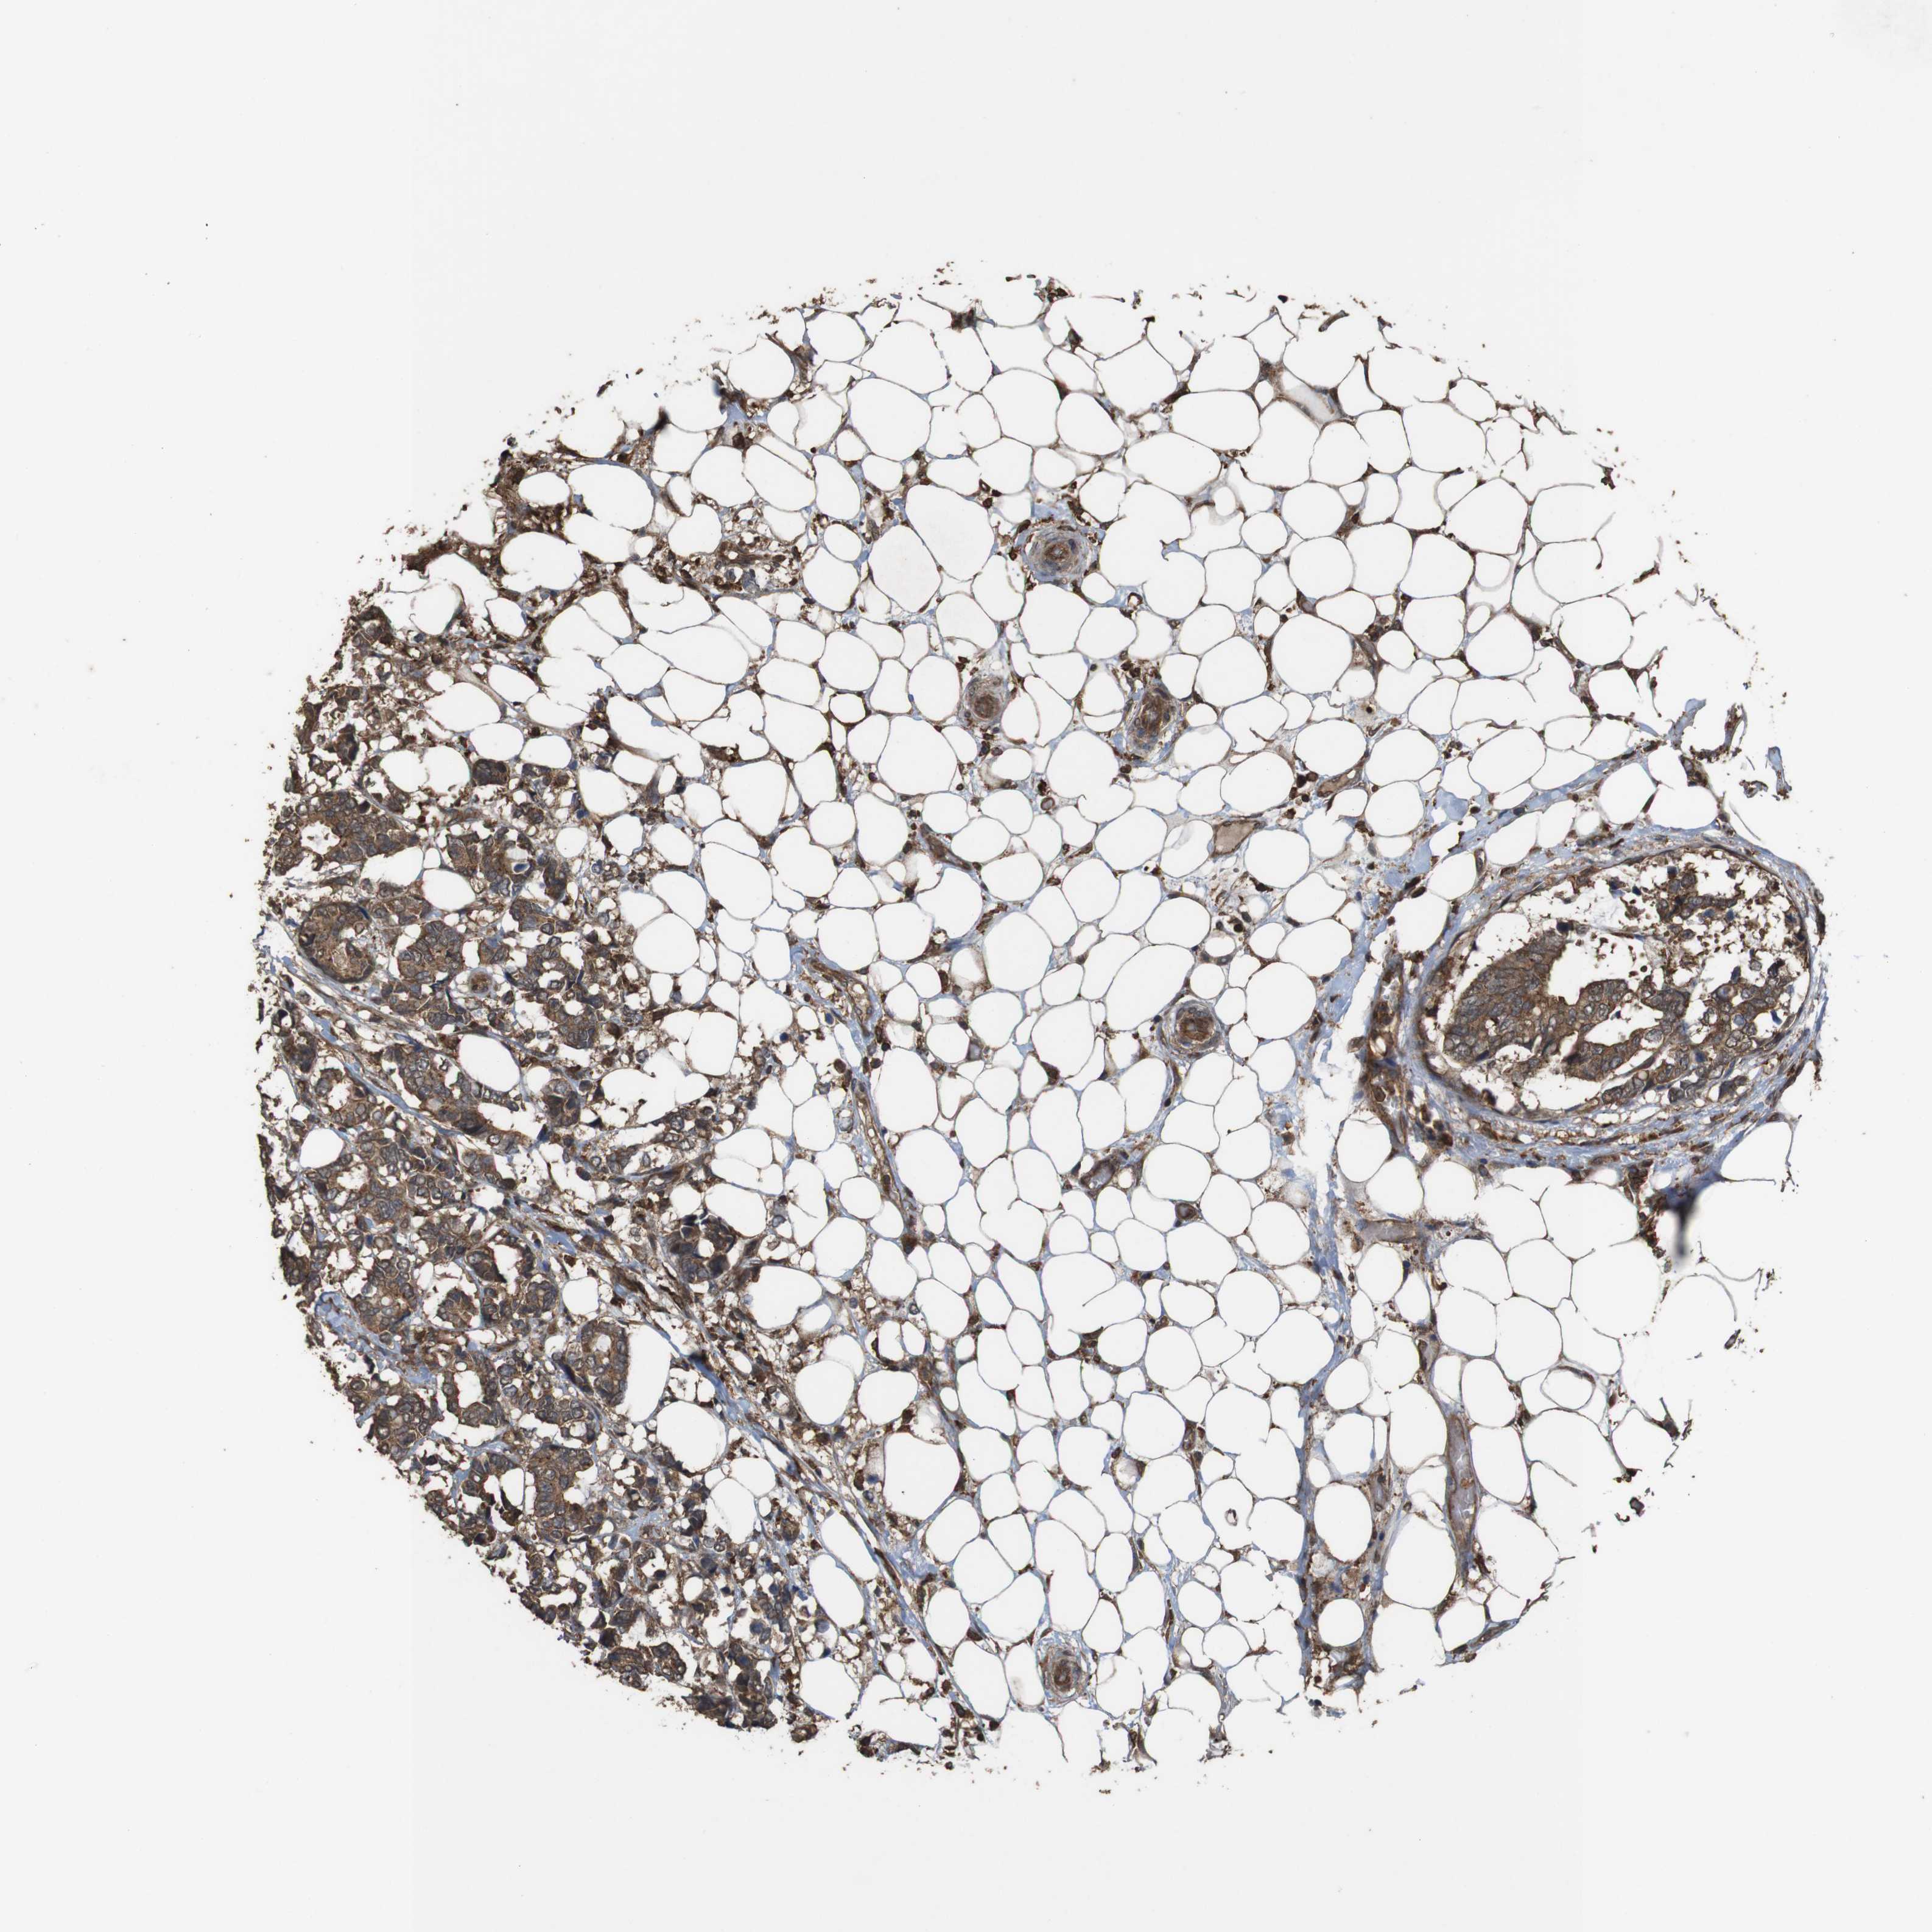

CANCER BREAST CANCER Show tissue menu

BRCA TCGA BRCA VALIDATION PROTEIN EXPRESSION